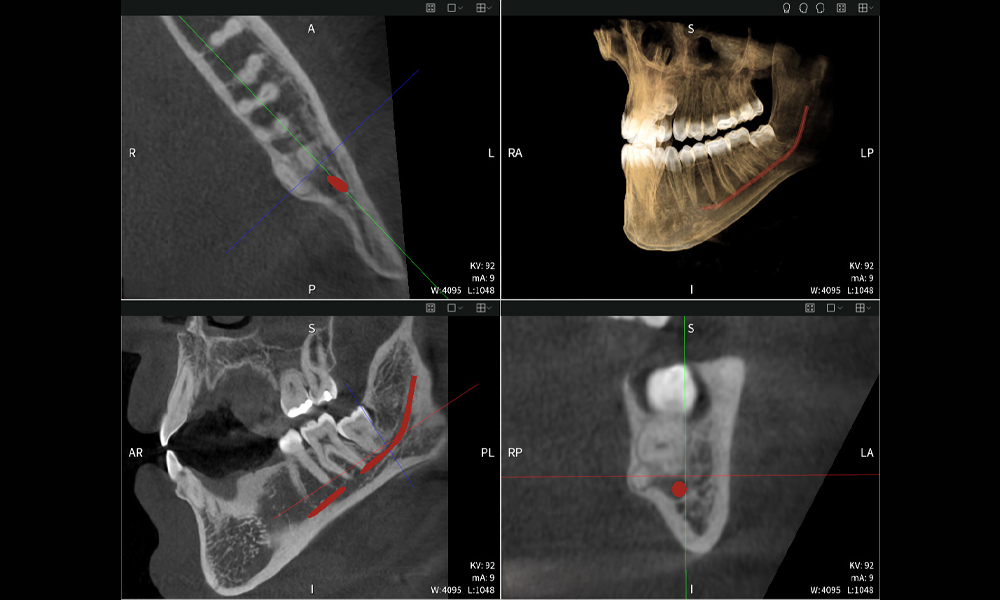

Figure d: Imaging results of Seethrough Max, in front of a black background.

Figure d

Figures b–d show various views of a 3D reconstruction of the mandible, providing a comprehensive overview of the mandibular anatomy, the position of the nerves in relation to the teeth, and allowing assessment of tooth symmetry and alignment.

Figure d shows the previously treated tooth 48, with its crown removed, and its roots left in proximity to the nerve, illustrating the high risk of nerve damage.